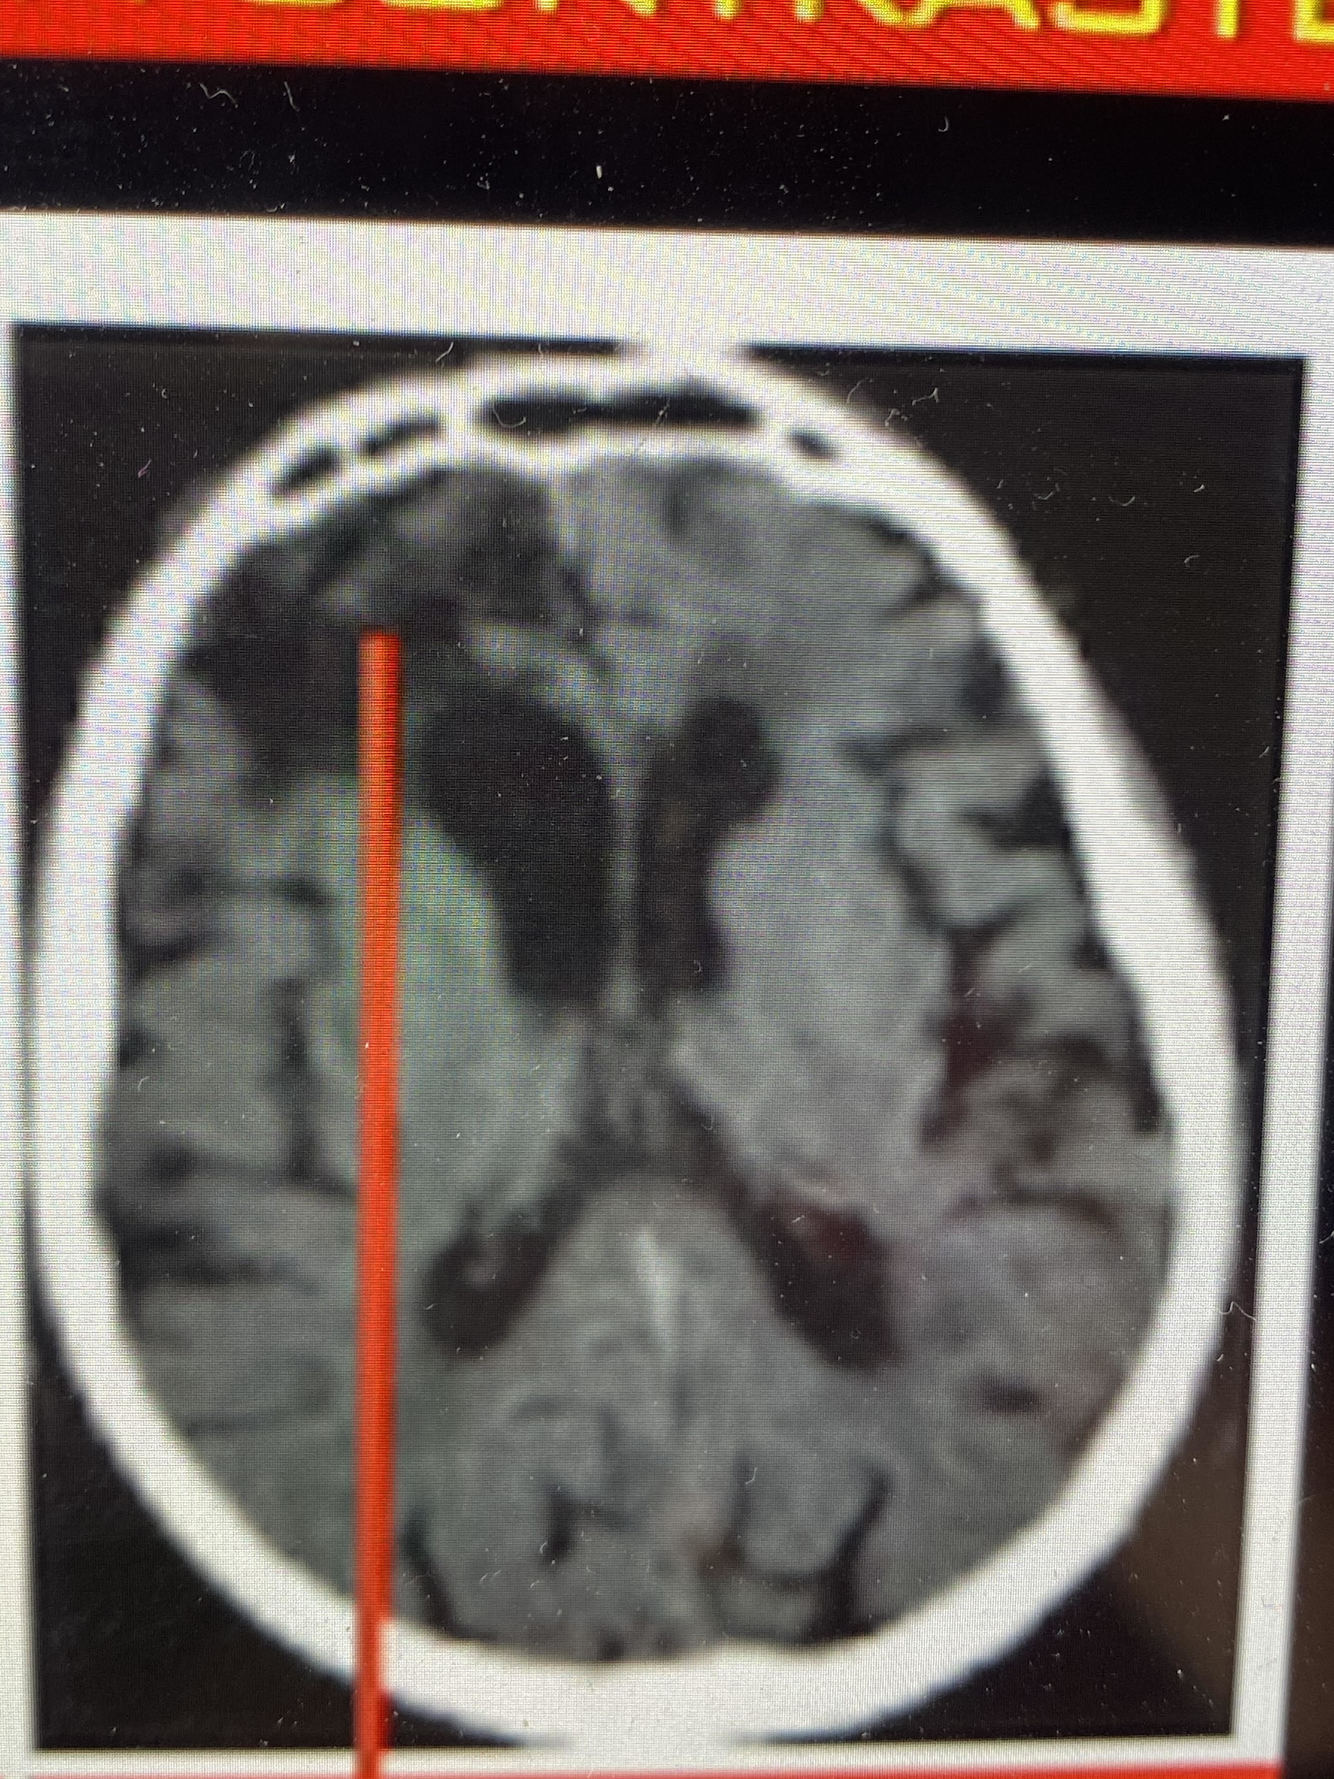

Qual artéria foi acometida? E qual seu Déficit?

A. cerebral posterior

Déficit visual

Quais artérias ou arteriolas foram acometidas nessa imagem? e o que causa?

Aa. Lenticulo - estriadas (AVE lacunar)

Hemiplegia contralateral pura (não tem outras manifestações)